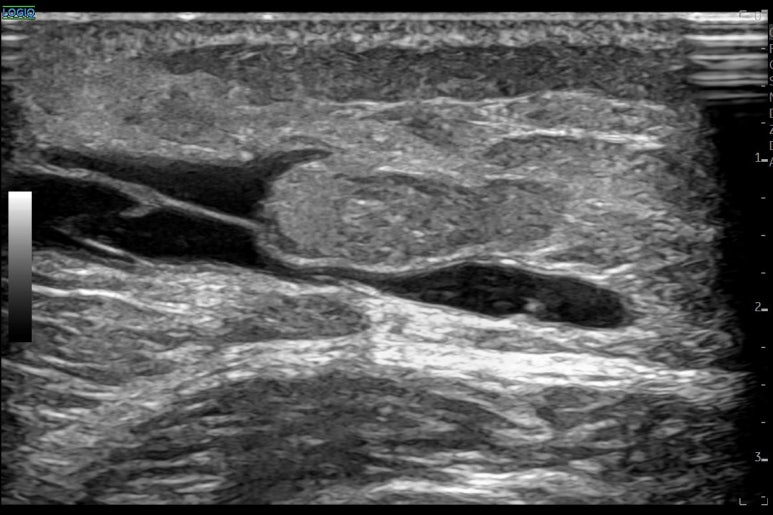

doi.org/10.2214/AJR.19.22752 혈종이 생긴 지 하루 된 것부터 최대 180일까지의 사례들을 분석한 결과, 이 기간 내에 발생한 것이라면 혈종의 '나이'가 시술의 성공 여부를 결정짓지는 않았습니다.

초음파상 피가 굳어 보이는 고에코 상태나 복잡한 격막이 관찰되더라도, 80% 이상의 사례에서 성공적으로 배액이 가능했던거죠. 배액술을 받은 모든 환자가 즉각적인 증상 호전을 보이기도 했고요. * * * ## 2가지 논문을 종합해본 결과즉, 6개월까지는 몸이 스스로 해결하려고 노력하는 기간이자 비침습적으로 해결할 수 있는 ## 이상적인 치료 기간인 셈입니다. * * * ## 5. 한의 초음파의 핵심경혈 주변을 정밀하게 타겟팅! 한의학에서는 이런 혈종을 치료할 때 '경혈' 주변의 해부학적 구조를 면밀히 살핍니다. 초음파를 통해 주변 근육인 경근(經筋) 조직의 손상이나 혈종의 정확한 깊이를 확인하는 것이죠. [하지부] 허벅지의 복토혈(伏兎) 엉덩이의 환도혈(環跳) 과 같은 주변에 깊숙이 자리 잡은 혈종은 손으로 만져서는 정확한 위치를 알기 어렵습니다.

초음파로 병변 부위에 딱 맞춰 시술해야 주변 조직 손상 없이 어혈을 빠르게 제거할 수 있고요. 치료 직후 혈종이 빠르게 사라집니다.